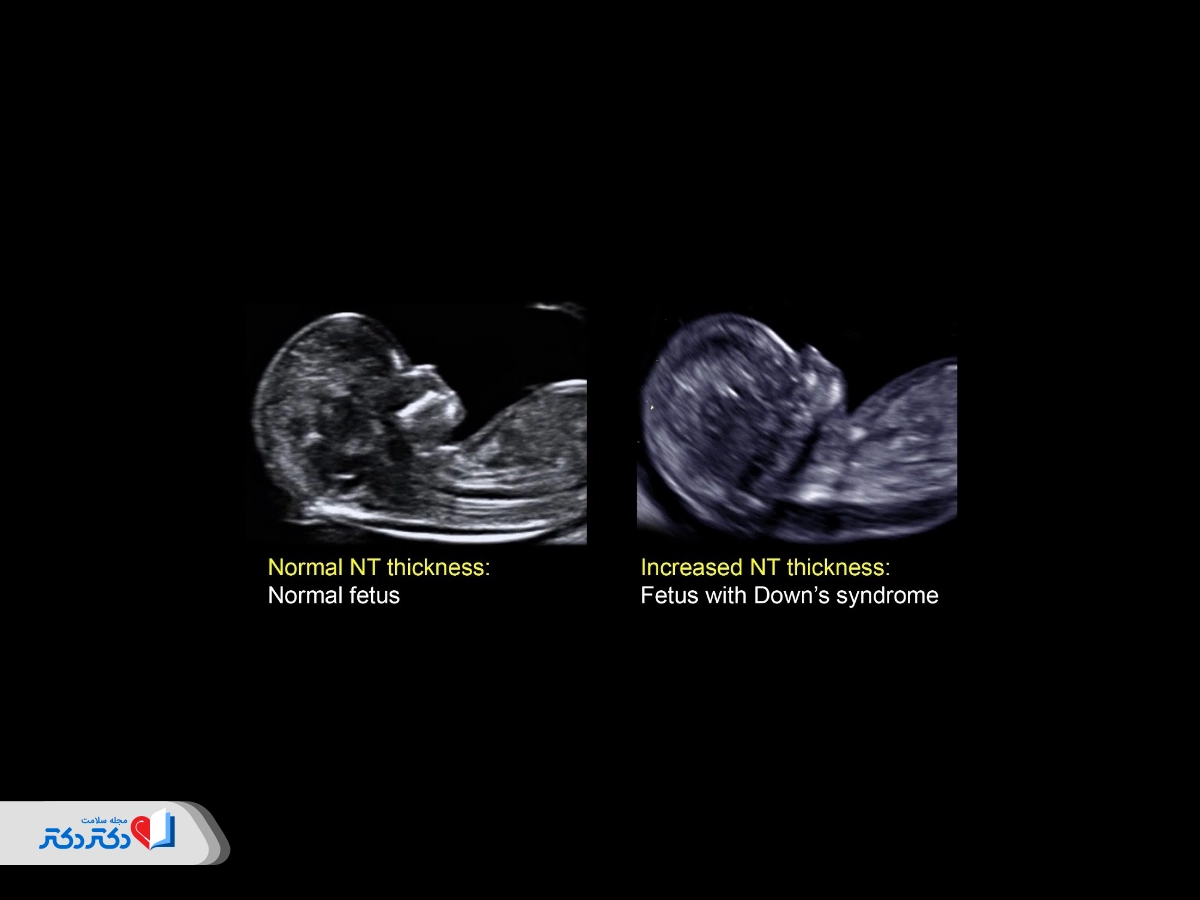

عکس سونوگرافی NT عادی و غیرطبیعی

عکس سونوگرافی ان تی

سونوگرافی ان تی به فضای پشت گردن نوزاد، که چین پشت گردن (nuchal fold) نام دارد، نگاه می‌کند. همه نوزادان مقداری مایع پشت گردن خود دارند؛ اما در جنین‌هایی که به اختلالات ژنتیکی و کروموزومی دچار هستند، مایع بیشتری در پایه گردن جمع می‌شود.